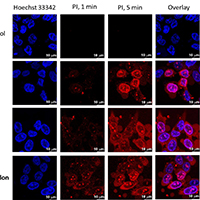

Тест на лимфоцитах из крови: ПИМУ и онкодиспансер Нижнего Новгорода прогнозируют эффективность иммунотерапии по свечению НАД(Ф)H. Biomedicines; грант РНФ 23-74-10109.